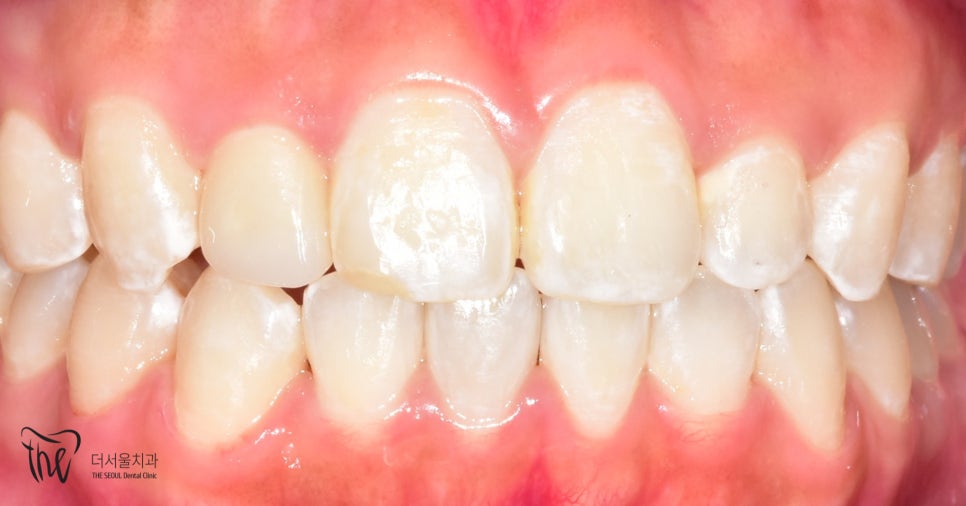

치료 후 모습을 보면

측절치가 서로 대칭인 것을 확인할 수 있으며

앞니가 가지런해 진것을 볼 수 있습니다.

치아교정 후

다시 틀어지지 않도록

고정식 유지장치를 붙여드렸습니다.

앞니 안쪽면에

가느다란 철사를 붙이는 방식으로

치아들이 다시 흐트러지는 것을

예방하는 역할을 하게 됩니다.